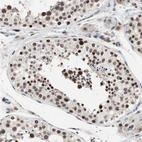

Immunohistochemical staining of human cerebral cortex shows strong nuclear positivity in neurons.